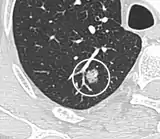

Low attenuating nodule (in this case a fat containing hamartoma).[9]

- Areas of fatty tissue (−40 to −120 HU) indicates a hamartoma. However, only about 50% of hamartomas are fat containing.[9]